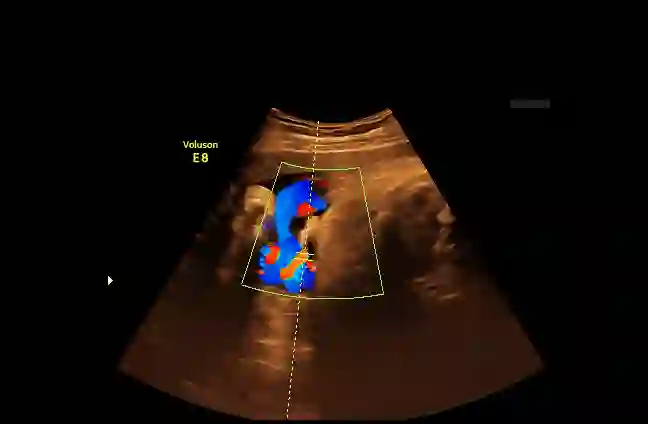

Examination of the umbilical artery with Doppler ultrasonography is performed to investigate blood supply to the fetus through the umbilical cord, which is vital for the monitoring of fetal health. Such examination involves several steps that must be performed correctly: identifying suitable sites on the umbilical artery for the measurement, acquiring the blood flow curve in the form of a Doppler spectrum, and ensuring compliance to a set of quality standards. These steps rely heavily on the operator's skill, and the shortage of experienced sonographers has thus created a demand for machine assistance. In this work, we propose an automatic system to fill the gap. By using a modified Faster R-CNN network, we obtain an algorithm that can suggest locations suitable for Doppler measurement. Meanwhile, we have also developed a method for assessment of the Doppler spectrum's quality. The proposed system is validated on 657 images from a national ultrasound screening database, with results demonstrating its potential as a guidance system.